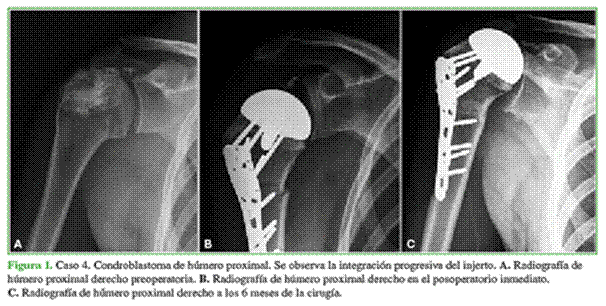

De acuerdo con los estudios radiográficos, ninguno tenía signos de infección del injerto o del sitio quirúrgico ni aflojamiento del material de osteosíntesis (Tablas 3 y 4, Figuras 1 y 2).

Se corroboró la correcta alineación del injerto en todos los casos. Así mismo, según la Escala de Osteointegración del ISOLS, la integración fue excelente en el 54% de los pacientes (7 casos), buena en el 23% (3 pacientes), aceptable en el 8% (1 caso) y pobre en el 15% (2 casos). En la Tabla 5, se detallan los resultados de cada paciente para la integración del injerto de acuerdo con la escala mencionada.